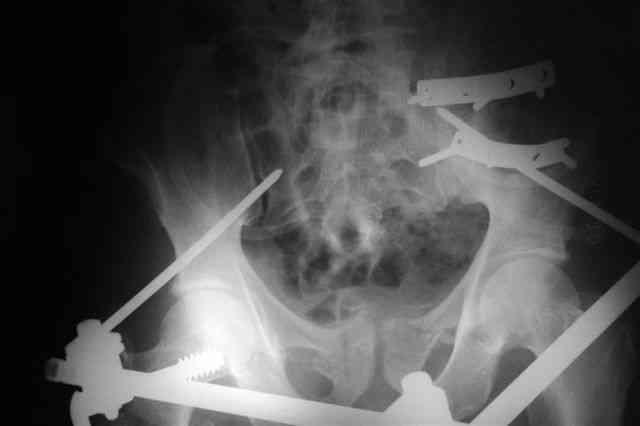

Вчера прооперировал больного.

Попытка низвести половину таза на тракционном столе ( скелетное вытяжение за бедро) безуспешная.

из переднего доступа добрался до правого КП сочленения , все запаяно костью, с помощью 2 шанцев винтов в крестец и подвздошную кость и элеватора репозиция, контроль ЭОП

и двумя пластинами фиксация.

Спереди, аппарат как рекомендовал Джолдас.

Снимки плохого качества( очень темные) завтра переделают и пришлю на конференцию.

На мой взгляд, смещение устранено и фиксация выглядит вполне анатомичной.

В приложении послеоперационные картинки.